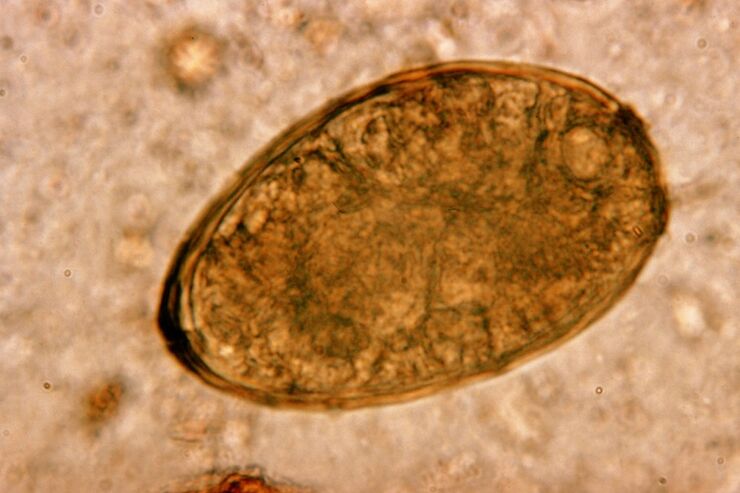

La douve vit par paires dans les poumons et forme des kystes dans les bronches. L'infestation se produit lors de la consommation de crabes et d'écrevisses infectés par le parasite. Une fois dans le tractus gastro-intestinal, la douve pulmonaire pénètre dans le péritoine et atteint les poumons par le diaphragme, provoquant une toux persistante chez le patient.

La petite douve pulmonaire helminthe, appartenant à la classe des trématodes, se « spécialise » dans le parasitisme spécifiquement dans les poumons. Il provoque des problèmes beaucoup plus graves au niveau du système respiratoire que les vers ronds, par exemple.

Sur le site de sa localisation, des infiltrats apparaissent et des hémorragies se développent, à la suite desquelles des cavités apparaissent remplies de métabolites en décomposition de vers, de parasites morts et de tissu pulmonaire. Les dommages causés par la douve pulmonaire sont encore aggravés par le fait qu’il s’agit d’un foie long et qu’il peut vivre dans le corps de l’hôte jusqu’à 20 ans.